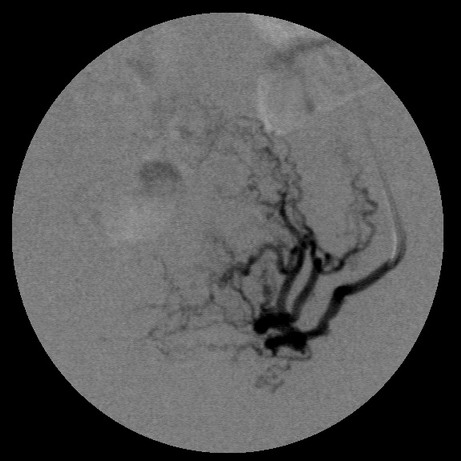

女,35岁,子宫多发肌瘤

子宫动脉增粗,分支数量增多,迂曲,染色明显并排空延迟

栓塞剂用的是进口pva,二瓶,几千块呀,栓塞面积应该不大吧,呵呵

左边没有避开卵巢支啊